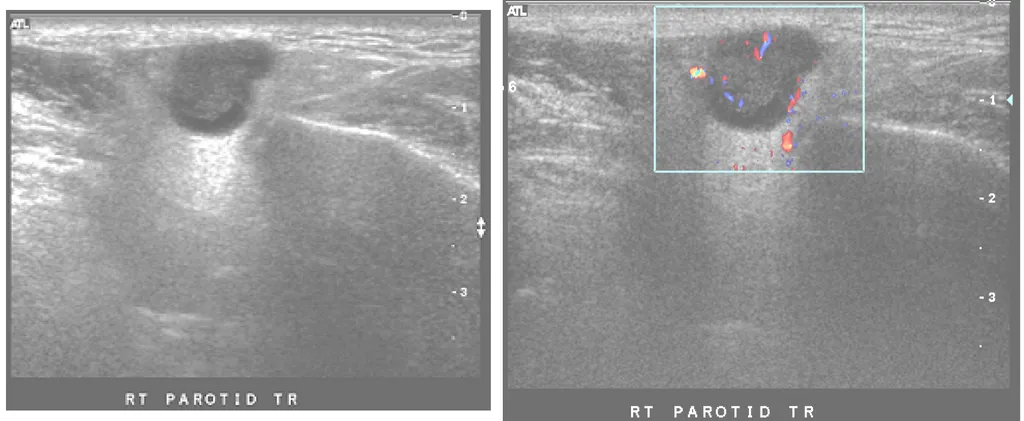

【112-1 醫學(六) 第74題】65歲男性病人主訴右臉耳下部位無痛硬塊約2年,耳下腺超音波檢查如圖,最可能的診斷為何?

這張超音波影像顯示耳下腺有一個邊緣清晰、內部實心的低迴音腫塊,且病患主訴是無痛且緩慢成長的硬塊,這些都是耳下腺多形性腺瘤的典型特徵。

-A:錯在耳下腺膿瘍通常會伴隨疼痛、發燒等發炎反應,且超音波下會呈現不規則邊緣的液體或複雜性囊腫,與圖中實心、邊緣清晰的腫塊不符。